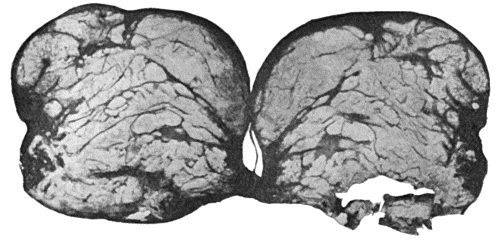

114.Section through Gouty Bursa 428